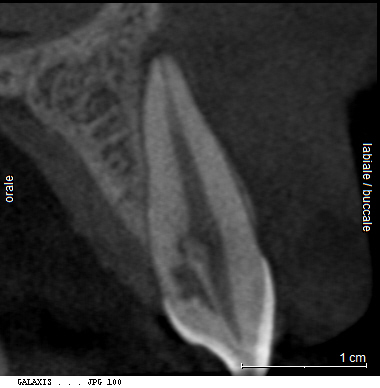

«L’imaging radiografico è fondamentale: dopo la raccolta dei dati anamnestici e un’accurata visita, il primo step è la radiografia periapicale eseguita con la tecnica dei raggi paralleli (centratori). Non sempre, tuttavia, questo esame consente di distinguere tra riassorbimento interno ed esterno; per questo è utile una seconda radiografia, con diversa inclinazione, che grazie alla sproiezione delle immagini può aiutare a chiarire il tipo di riassorbimento. Oggi però sappiamo che l’immagine bidimensionale presenta molti limiti; per questa ragione, le principali linee guida internazionali (AAE-American Association of Endodontists ed ESE-European Society of Endodontology) raccomandano un esame di secondo livello come la CBCT (FOV piccolo, alta risoluzione). Questo consente una diagnosi precisa, informazioni sulla reale estensione del processo distruttivo e, di conseguenza, un piano di trattamento più accurato».

Dal punto di vista biologico, i riassorbimenti derivano dall’attivazione di cellule clastiche capaci di degradare dentina e cemento, stimolate da fattori infiammatori o traumatici. «Le cause più comuni sono traumi, movimenti ortodontici, scaling e carie, ma talvolta il processo decorre del tutto senza sintomi. Clinicamente, i riassorbimenti radicolari possono restare occulti a lungo e venire diagnosticati solo con indagini radiografiche o, più recentemente, con CBCT, che ha migliorato la comprensione di localizzazione ed estensione del difetto, distinguendo chiaramente tra quadri interni ed esterni, distinzione fondamentale per strategie e prognosi».

Per questo oggi si raccomanda una valutazione accurata dell’estensione del riassorbimento con CBCT, l’uso di sistemi ottici ingrandenti, irrigazioni attivate e materiali bioceramici ad alta biocompatibilità e adattamento marginale.